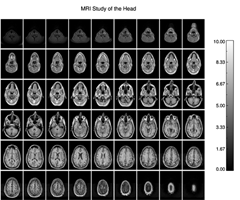

Multiple Image Plot *** Multiple Image Plot *** Additional Information